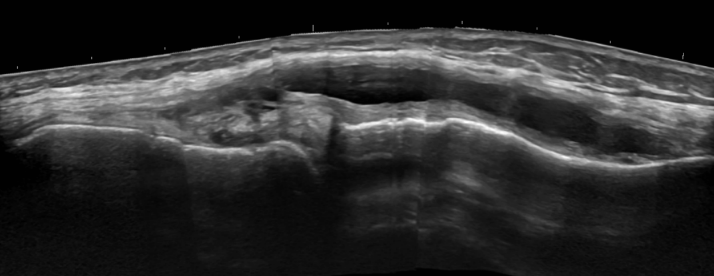

3. Large parameniscal cyst